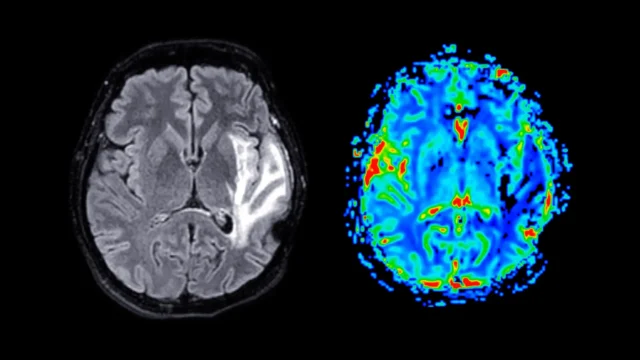

A imagem cerebral mostra uma redução significativa no volume de substância cinzenta em mulheres na pós-menopausa, independentemente de usarem ou não terapia de reposição hormonal. A substância cinzenta contém corpos de células nervosas e desempenha um papel fundamental no processamento de informações, no controle do movimento, no apoio à memória e na regulação das emoções.

As áreas mais afetadas incluem o hipocampo (responsável pela formação e armazenamento de memórias), o córtex entorrinal (a “porta de entrada” de informações entre o hipocampo e o resto do cérebro) e o córtex cingulado anterior (a parte do cérebro que ajuda a gerenciar emoções, tomar decisões e focar).